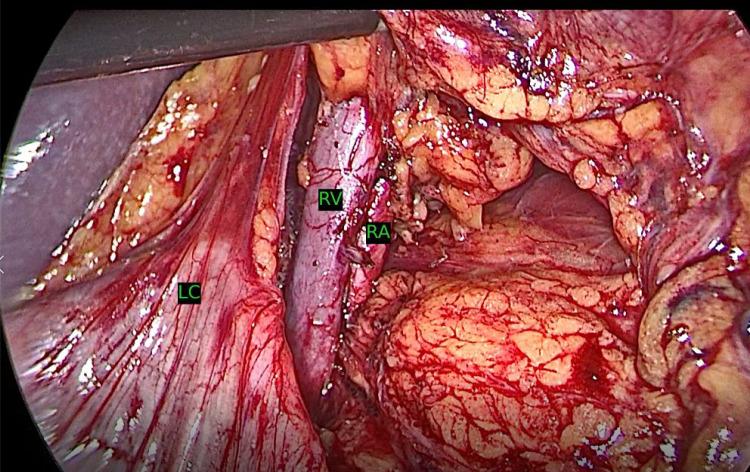

Objective: Laparoscopic donor nephrectomy has become a standard of care for living kidney donors, providing reduced morbidity, quicker recovery, and enhanced patient satisfaction compared with open techniques. This study evaluates a modified laparoscopic donor nephrectomy technique designed to minimize colon mobilization while optimizing visualization, thereby improving donor outcomes. Methods: A cross-sectional study of 250 consecutive living donor nephrectomies performed by a single surgeon between March 2022 and March 2024 was conducted. All donors underwent preoperative imaging (3D computed tomography and computed tomographic angiography). The modified approach avoided splenic flexure dissection and introduced early ligation of the adrenal vein. We analyzed intraoperative parameters (operative time, estimated blood loss, complications) and postoperative measures (hospital stay, pain scores, complication rates, satisfaction) were analyzed. Results: The mean operative time was 72.8 ± 16.2 minutes, with an estimated blood loss of 100 ± 40 mL. No conversions to open surgery or intraoperative transfusions were required. The mean length of hospital stay was 2.0 ± 1.0 days. Postoperative pain (mean Visual Analog Scale [VAS] 2.5 ± 1.8) was low, and major vascular injury occurred in 0.8% of cases. Wound infection and incisional hernia rates were each 0.8%. Patient satisfaction was high (Patient Satisfaction Questionnaire [PSQ] 3.3 ± 1.4), indicating favorable perceptions of comfort and outcomes. Conclusion: This modified laparoscopic donor nephrectomy technique is safe, effective, and associated with enhanced patient comfort and reduced complications. The findings underscore its potential to improve donor experiences, potentially expanding the living donor pool. Further investigations should confirm these outcomes over a longer follow-up period.

目的